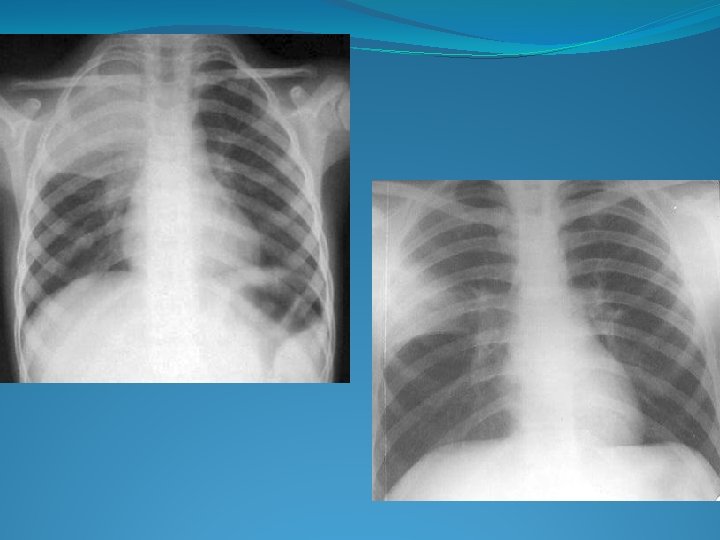

Examen radologic �in pneumonia lobara sau segmentara opacitatea subcostala bine delimitate, omogena in stadiile incipiente; �in bronhopneumonie unice sau multiple opacitati disseminate, de diferite marimi, forma, intensitate cu contur neclar, neomogene si variabile �in pneumonia interstitiala

Bronhopneumonie Pneumonie lobară Reprezentarea schematică a bronhopneumoniei şi pneumoniei lobare

Radiologic: opacitati rotunde/ovalare, contur estompat, diseminate opacităţi multiple de intensitate medie, numeroase în câmpurile pulmonare medii şi bazale opacităţi difuze, mai frecvent in c. pulmonare superioare ca şi in regiunile parahilare

BRONHOPNEUMONIE